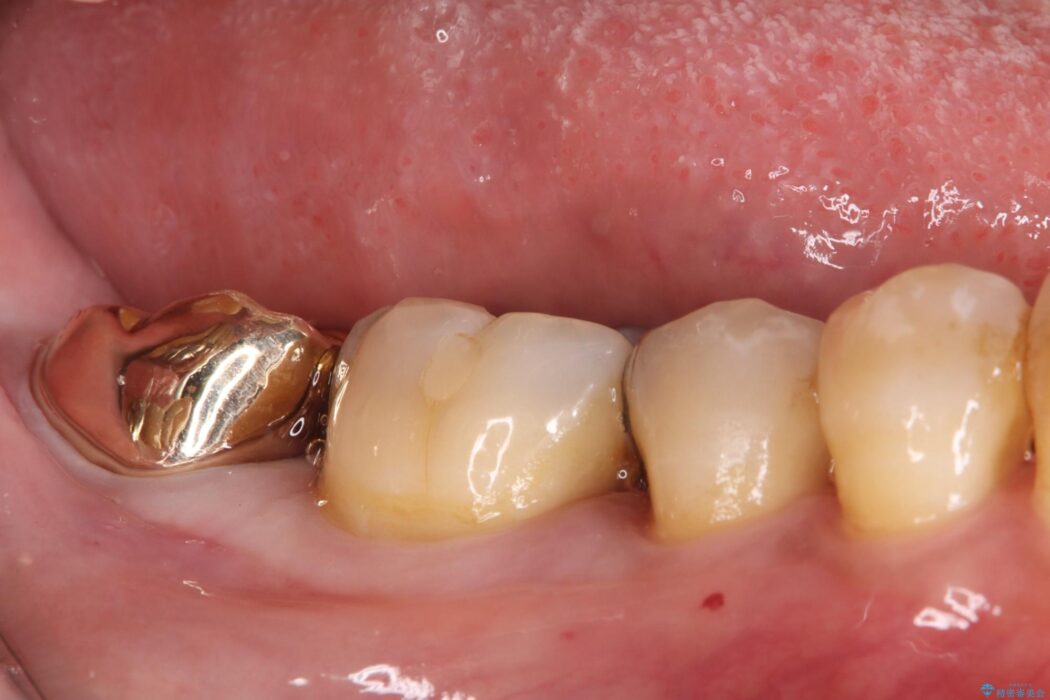

以前治療した奥歯(右下7番)の詰め物が欠けてしまったとご来院された患者様です。

検査の結果、残存歯質が少なく破折リスクが高いため、歯全体の補強が必要と診断しました。強い咬合力に耐えられるよう、適合性と強度に優れたPGAクラウンによる修復を計画しました。これにより、二次カリエス(虫歯の再発)や破折を防ぎ、奥歯の機能を長期的に安定させます。